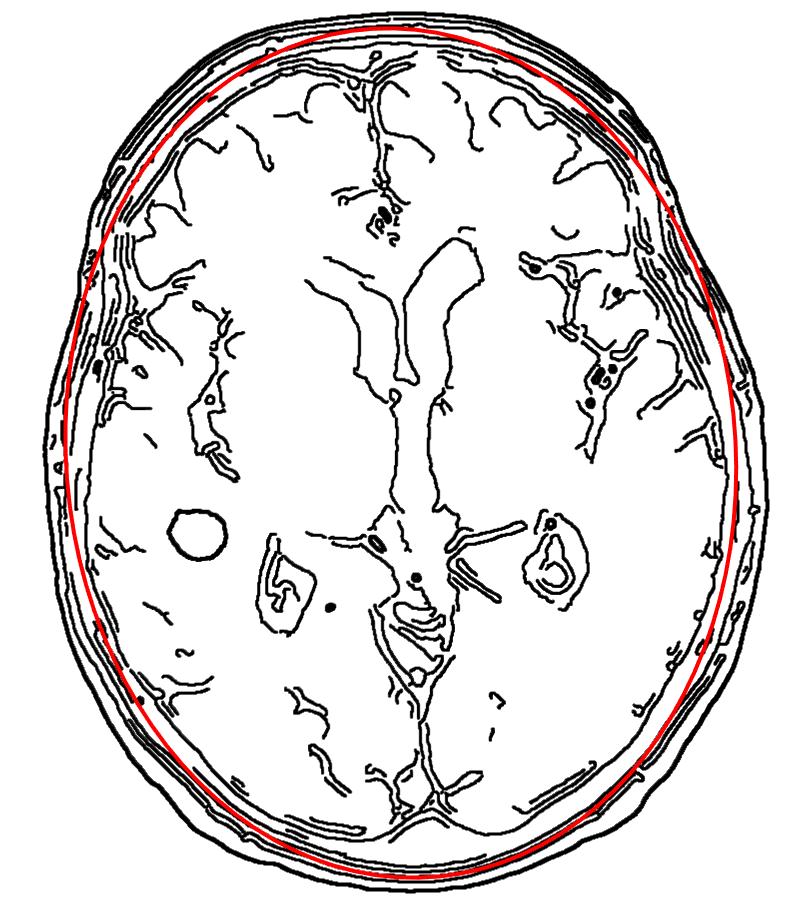

4.1.7 Application on Cell Counting

Finally, BayFit is deployed for cell counting in microscopy images, where multiple ellipse fittings are required. We conduct tests on both fluorescence and blood cell modalities, as depicted in Figs. 14 and 15, respectively. The used fluorescence images are collected by [52], while the blood cell images are sourced from the American Society of Hematology (ASH) image bank [53]. BayFit is applied to the edge maps of these images and returns ellipses one by one. In the bottom row of Fig. 14, BayFit not only delivers satisfactory approximations to various cell shapes but also provides highly accurate counts of the cell quantities. Even in challenging environments with a large number of irregular and small cells (Fig. 15), BayFit still demonstrates its potential in automating the labor-intensive task of cell counting. It is noticeable that our ellipse fitting approach in this context is a general-purpose algorithm that does not resort to additional application-related information or post-verification, such as shape or appearance constraints, which may further facilitate the performance. Other two applications including 3D reconstruction and elliptical object approximation are presented in Section 12.1 of the Supplementary Material.